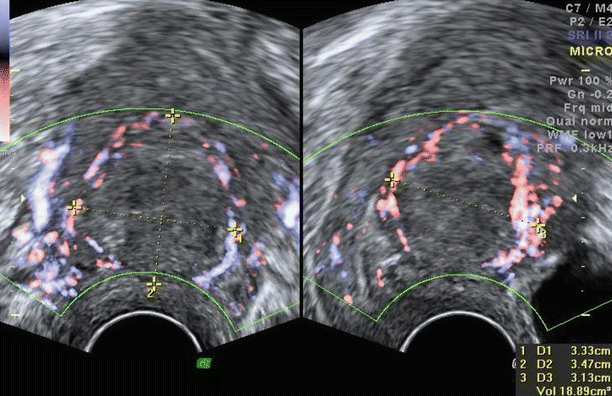

The arcuate vessels can be seen in the outer part of the myometrium running parallel to the serosa. Perpendicular to the arcuate vessels are the radial arteries and veins. Flow can be seen in these arcuate and radial vessels of the myometrium. Power Doppler is preferred to colour Doppler in assessing flows in the myometrium because power Doppler is more sensitive to detect flows in small vessels and low-velocity flows.

Whenever a lesion is visualised, its vascularity should be reported using subjective colour scoring from 1 to 4 (discussed in detail in Chap. 2 under the section on Doppler). One can also do a spectral flow analysis to assess resistance to flow (RI or PI) and flow velocity (PSV) in a vessel.

Lesions of the myometrium may show circumferential flow running along the periphery of the lesion or intralesional flow running through the mass.

Fig. 3.6

Normal vasculature of myometrium on (a) colour Doppler and (b) on 3D glass body display. Short thick arrows showing arcuate vessels, medium-sized arrows showing radial vessels and long arrows showing spiral vessels